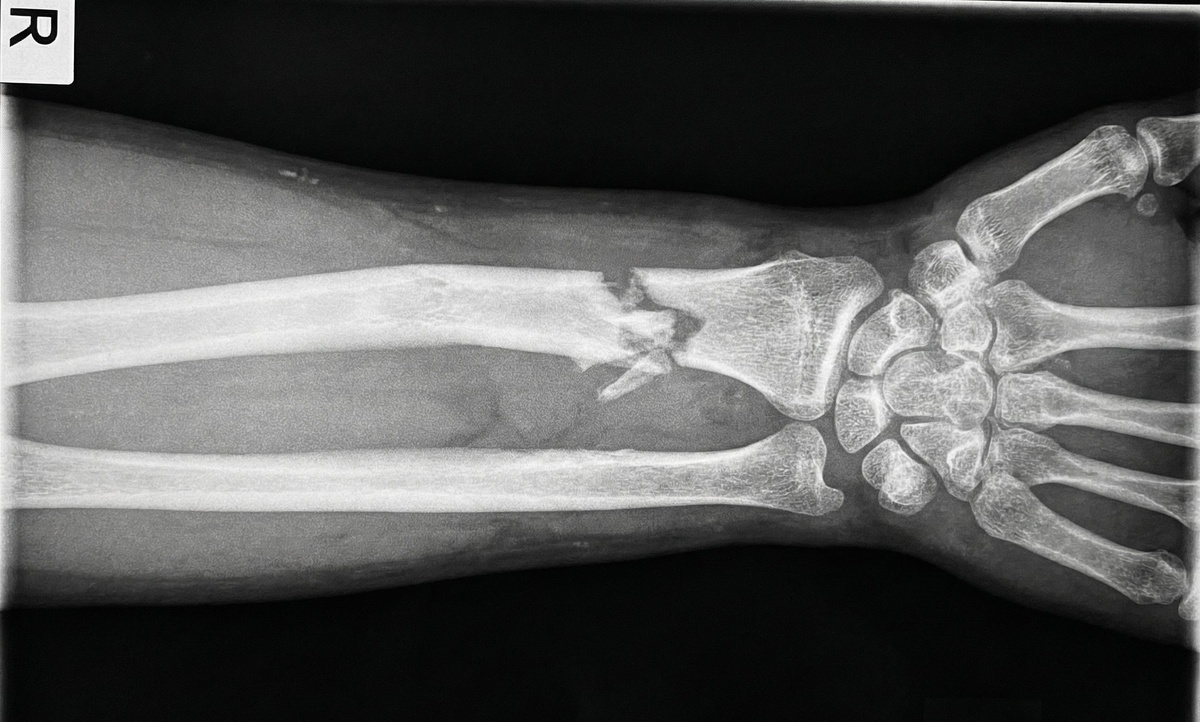

Зимний Петербург прекрасен, но, к сожалению, гололед — суровая реальность. Ежедневно в травмпункты обращаются десятки людей с ушибами, вывихами и, конечно, переломами. Самый частый сценарий: поскользнулся, неудачно выставил руку, и вот она уже висит «плетью», а на рентгене — перелом лучевой кости в типичном месте со смещением.

Фото рентгена перелома лучевой кости

Главное показание — перелом со смещением. Увидеть его можно только на рентгеновском снимке. Если отломки разошлись, их необходимо сопоставить. Это касается переломов самых разных костей:

• Лучевой кости в «типичном месте» (самый частый зимний перелом).